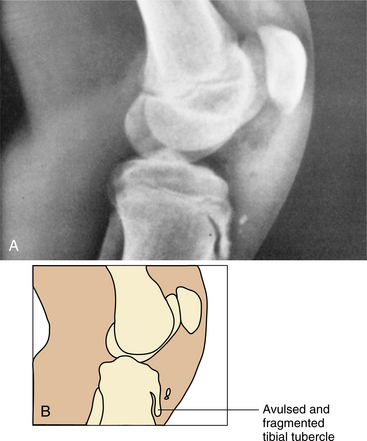

In young athletes, the tendon is attached to prebone, which is weaker than normal adult bone. With excessive stresses on the tendon from running and jumping, the structure becomes irritated and a tendinitis begins. Often fragments representing cartilage or bone formations are found on the surface of the patellar tendon and are a potential cause of pain. These patellar tendon fibers can actually pull fragments away from the tibial epiphysis (Fig. 27-29).

Figure 27-29 Clinical radiograph of the knee in a 12-year-old child shows fragmentation and avulsion of the tibial tubercle. Swelling below the knee and an enlarged tibial tuberosity may be observed clinically. This condition, known as Osgood-Schlatter disease, is probably posttraumatic. (From Bullough PG: Orthopaedic pathology, ed 3, London, 1997, Mosby-Wolfe, p 98.)